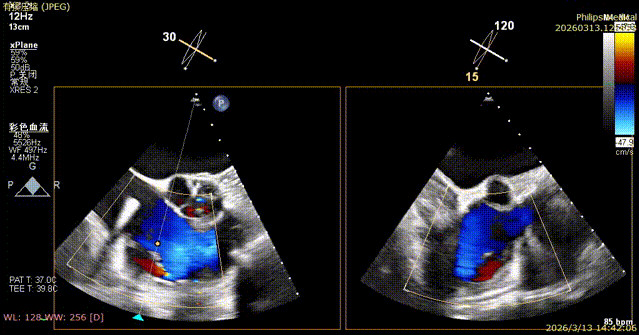

Postoperative regurgitation baseline

Following annuloplasty, leaflet coaptation was improved compared with the preoperative state, and regurgitation was reduced from severe to trivial.

1. The tricuspid annulus was significantly reduced, and the degree of regurgitation was reduced from severe to trivial, with a marked improvement in regurgitation. Although the coronary artery course was somewhat affected intraoperatively, blood supply remained normal. For patients at high coronary risk with concomitant tricuspid regurgitation, the outcome exceeded expectations and successfully alleviated the patient’s burden.